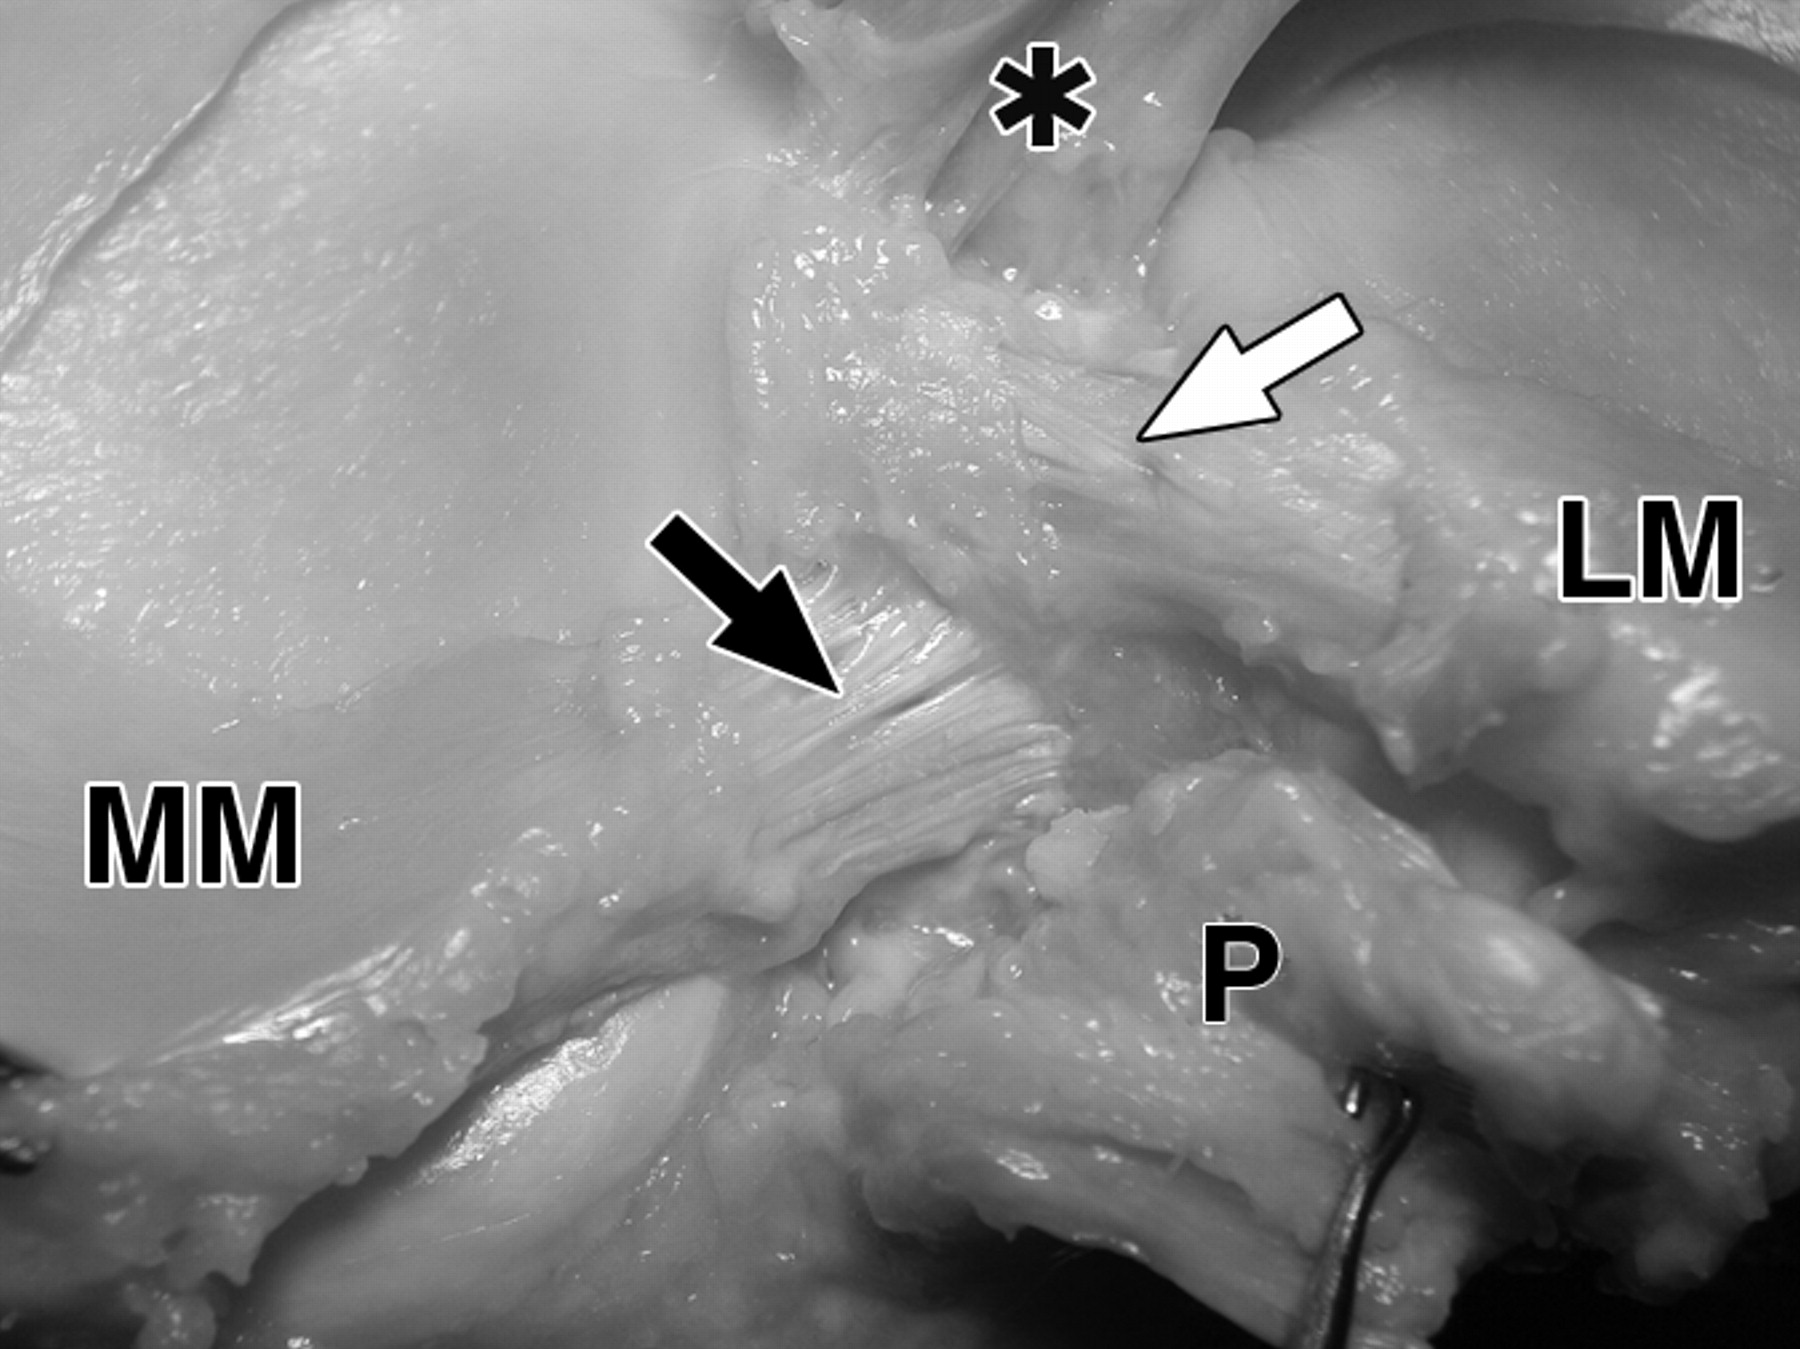

图1B-59岁男性大体标本。

黑色长箭头表示内侧半月板(MM)前根;黑色短箭头表示内侧半月板后根;白色长箭头表示外侧半月板(LM)前根;白色短箭头表示外侧半月板后根。主视图显示了与前交叉韧带(星号)、后交叉韧带(P)、后股关节Wrisberg韧带(黑色箭头)和膝横韧带(白色箭头)的关系。

图4A-59岁男性大体标本。

照片显示了前、后交叉韧带胫骨止点的解剖关系。

图4 B-59岁男性大体标本。

膝关节后视图显示外侧半月板后根(LM)(白色箭头)的止点比内侧半月板后根(MM)(黑色箭头)和后交叉韧带(P)的止点更靠前。前交叉韧带止点(星号)在结节间嵴的前面,但由于摄影变形,看起来更靠近外侧半月板后根。

图4C-59岁男性大体标本。

去除交叉韧带后的膝关节后视图对应于B。长白色箭头表示外侧半月板(LM)的前根。短白色箭头=外侧半月板后根,黑色箭头=内侧半月板后根(MM),MT =内侧胫骨结节,LT =外侧胫骨结节,P =后交叉韧带。